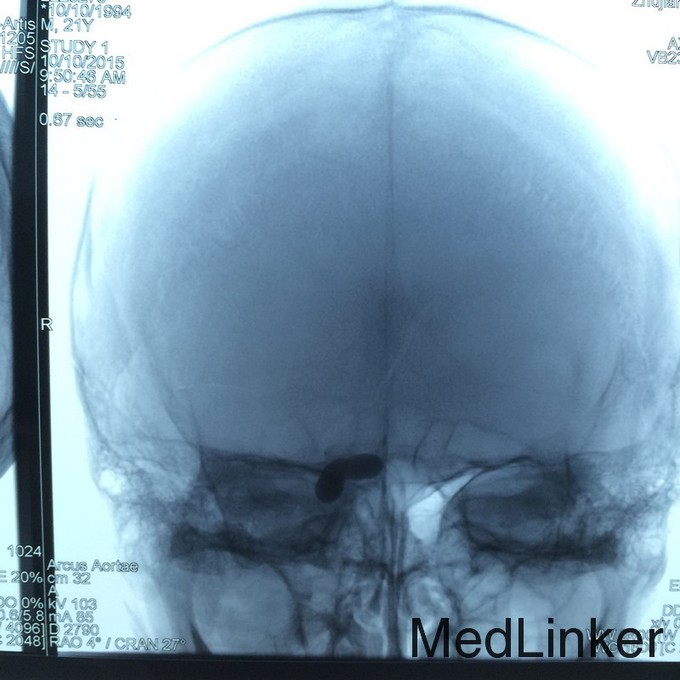

查体:右侧眼球突出,伴外展活动受限 辅助检查:头颅DSA提示右侧CCF

诊断:右侧自发性颈动脉海绵窦瘘 治疗:行头颅DSA检查,并用可脱性球囊将瘘口栓塞治疗